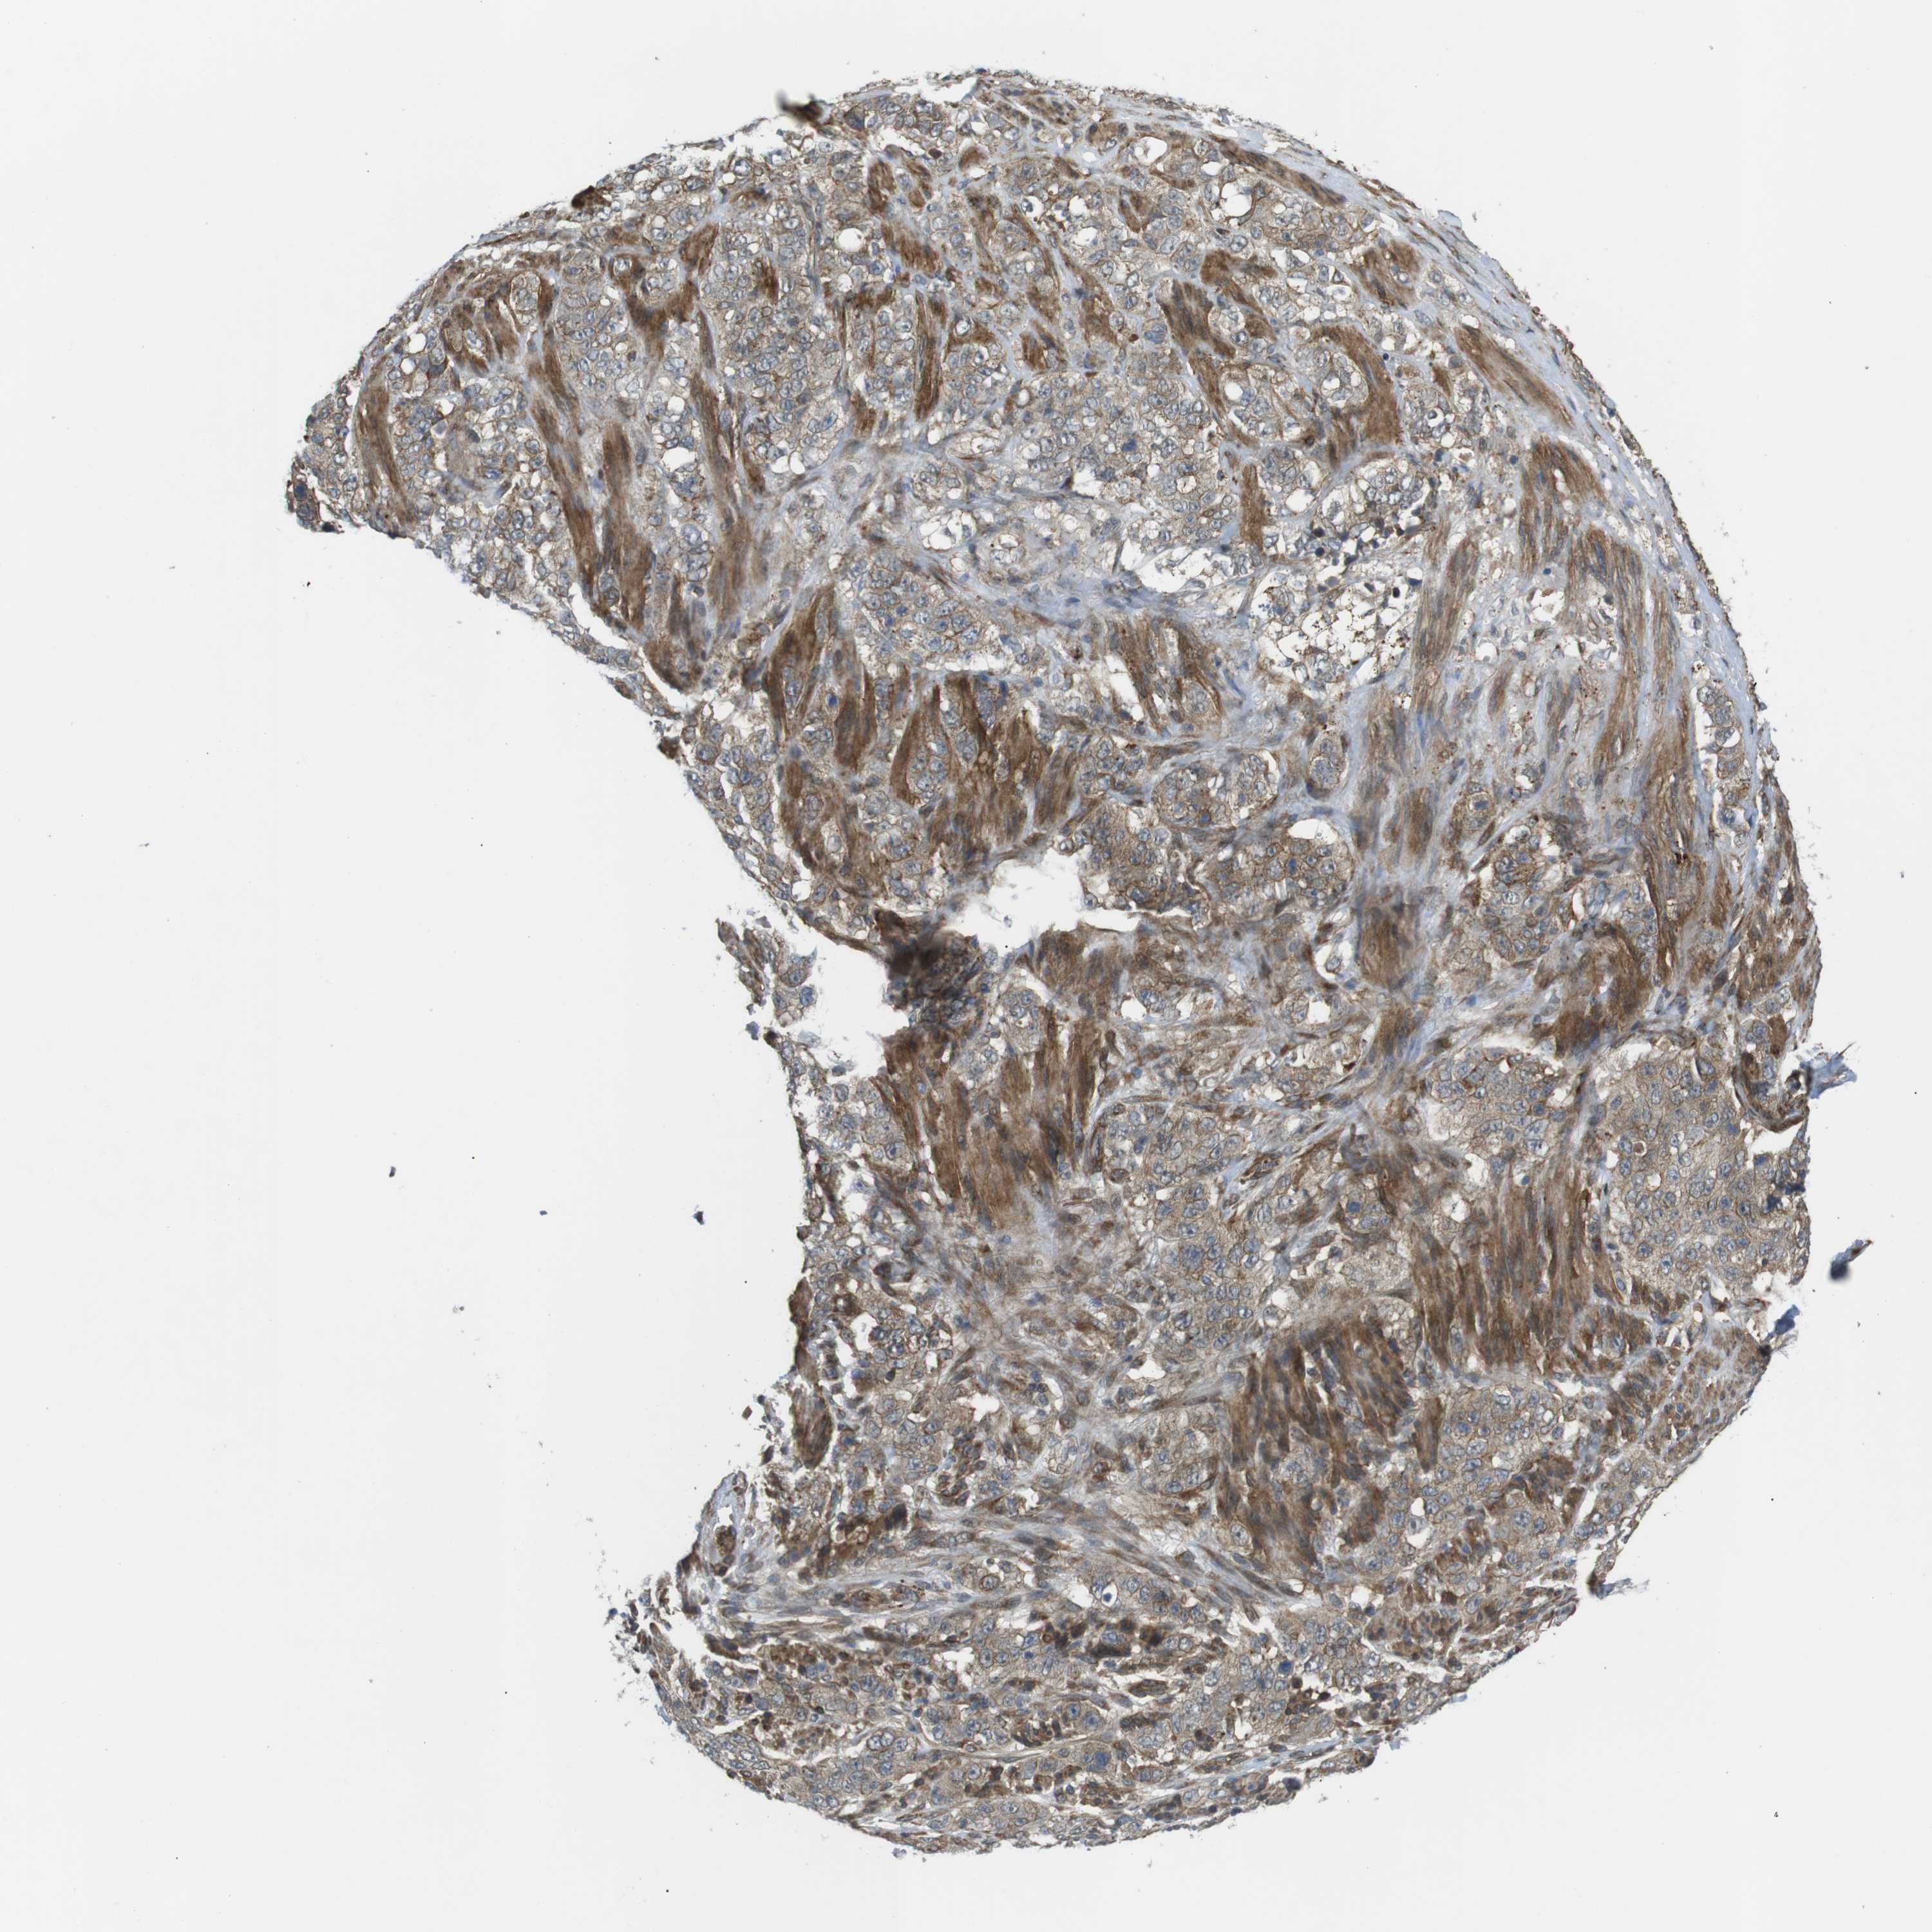

STOMACH CANCER - Protein expressioni

A mouse-over function shows sample information and annotation data. Click on an image to view it in a full screen mode. Samples can be filtered based on level of antibody staining by selecting one or several of the following categories: high, medium, low and not detected. The assay and annotation is described here.

Note that samples used for immunohistochemistry by the Human Protein Atlas do not correspond to samples in the TCGA dataset.

Antibody stainingi

Antibody staining in the annotated cell types in the current human tissue is reported as not detected, low, medium, or high, based on conventional immunohistochemistry profiling in selected tissues. This score is based on the combination of the staining intensity and fraction of stained cells.

Each image is clickable and will lead to virtual microscopy that enables deeper exploration of all samples and also displays staining intensity scores, fraction scores and subcellular localization as well as patient and tissue information for each sample.

Antibody HPA015643

Staining

High

Medium

Low

Not detected

Intensity

Strong

Moderate

Weak

Negative

Quantity

>75%

75%-25%

<25%

None

Location

Nuclear

Cytoplasmic/membranous

Cytoplasmic/membranous,nuclear

Adenocarcinoma, NOS